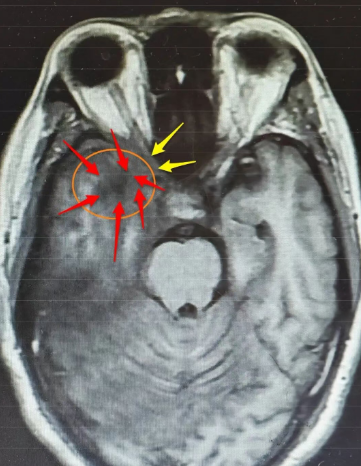

入院后,神经外科王典春主任为他完善了相关检查,对比院外之前的检查结果,发现他的右侧颞叶病变较前明显扩大,长径已达54mm,且顶叶、枕叶发展,邻近脑膜增厚明显,“从影像学表现及实验室检查看,炎性病变可能性不大,再结合患者症状进行性加重的特点,胶质瘤也不能排除。”王典春主任在病例讨论中强调,右侧颞叶的占位性病变已压迫视神经,这正是导致李先生右眼失明的关键原因,若不及时干预,不仅视力恢复无望,病变还可能进一步侵犯脑组织,威胁生命安全。

虽然仍未完全明确病变性质,但神经外科专家团队一致认为,手术是当前最关键的治疗手段 ——通过手术切除部分颞叶病变组织进行术中冰冻及病理活检,可直接明确诊断,同时实施右侧视神经减压术,能缓解病变对神经的压迫,为视力恢复创造可能。

在麻醉团队的密切配合下,王典春主任凭借丰富的临床经验与精湛的操作技巧,小心翼翼地通过右侧翼点入路进入颅内,精准定位右侧颞叶病变区域,在保护周围正常脑组织与神经的前提下,成功切除部分病变组织送检,同时王主任还对受压的右侧视神经进行了细致减压,手术过程顺利。

最终术后病理报告也证实了李先生真正的病因是右侧颞顶枕叶的节细胞胶质瘤(WHO1级),这一结果为后续治疗提供了明确方向,神经外科专家团队将根据李先生手术后的恢复状况,联合肿瘤科等多个相关科室共同为他制定个性化的综合治疗方案,进一步控制病情发展。